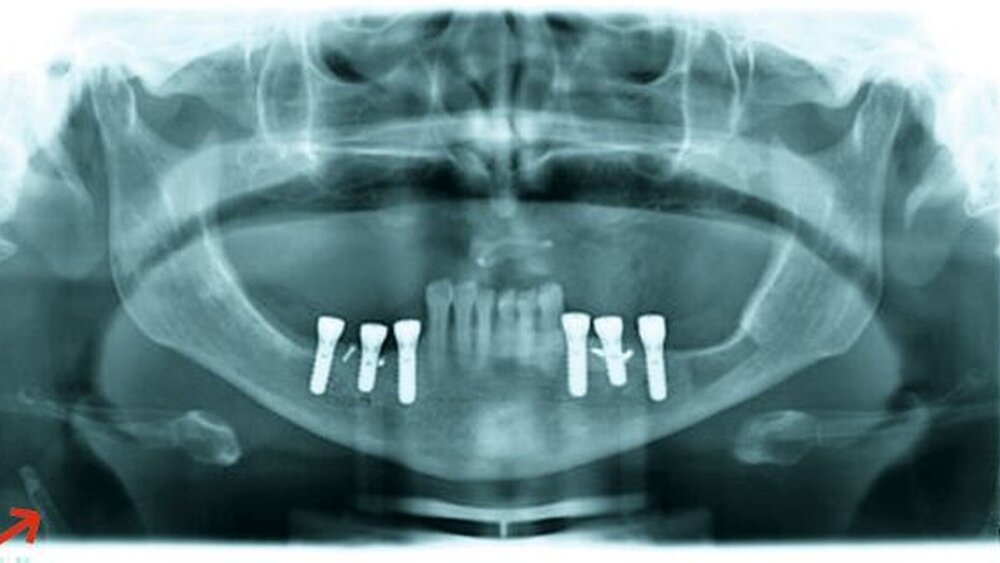

• Carotissklerose im OPTG beachten und eine neurologische Diagnostik veranlassen